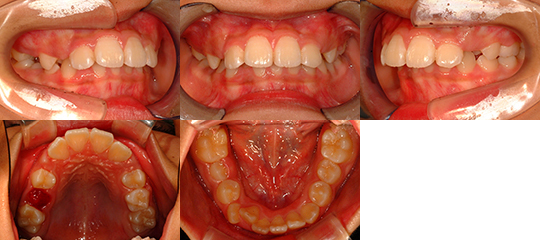

第二期治療(上下顎マルチブラケット矯正装置)開始時

第二期治療終了時

治療後1年4か月時